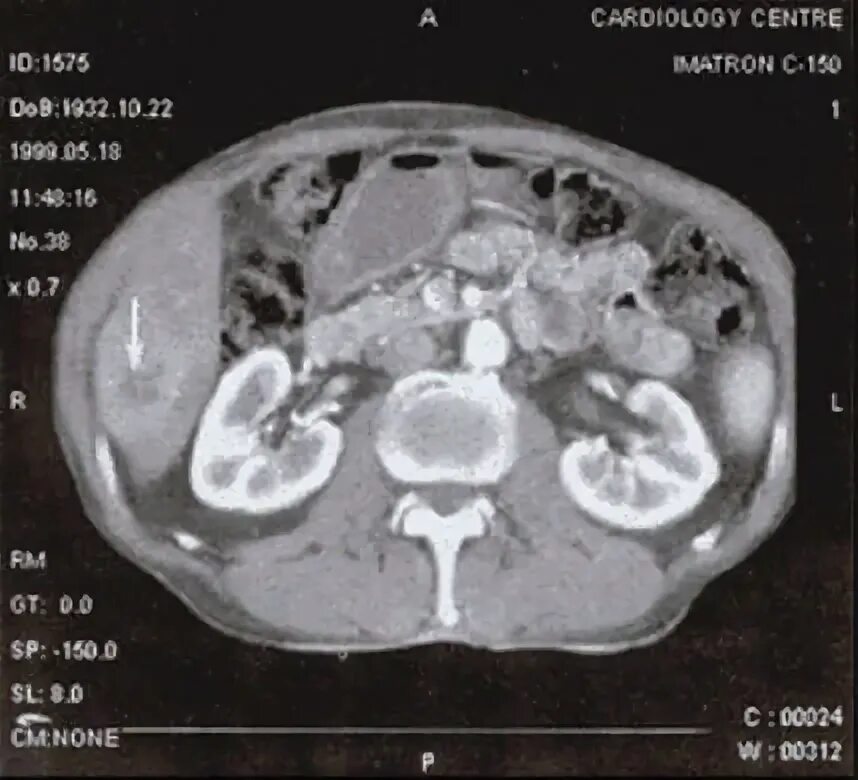

Плотность печени на кт